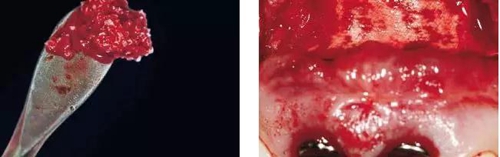

圖9、頰側(cè)骨壁用自體骨覆蓋,Geistlich Bio-Oss®覆蓋在自體骨的外側(cè),Geistlich Bio-Oss®同樣也要放置在基臺(tái)與牙齦之間,以支撐牙齦的外形。

圖10、為了避免對植骨區(qū)的干擾,外側(cè)覆蓋Geistlich Bio-Gide®膠原膜。

圖11、穿黏膜愈合1周后,牙齦外形良好。